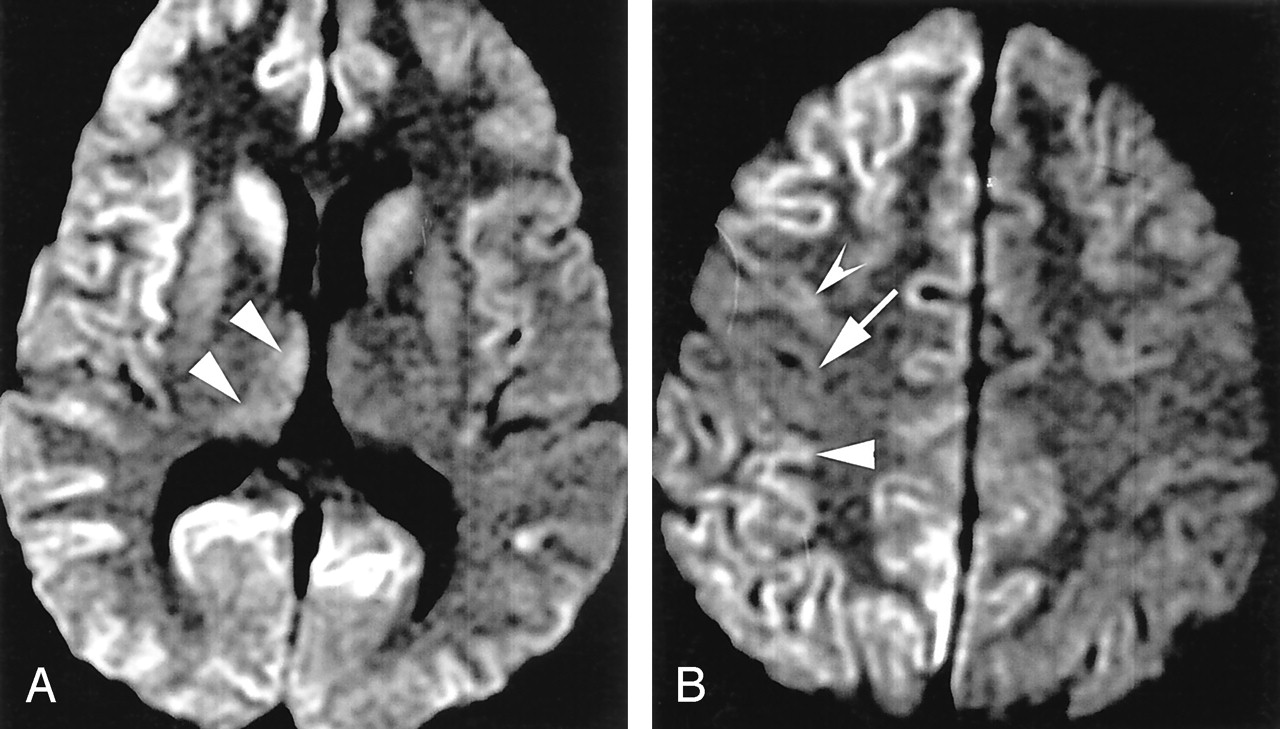

Болезнь Нимана-Пика Тип А: Симптомы и лечение

Раздел: Визуальный дайджест